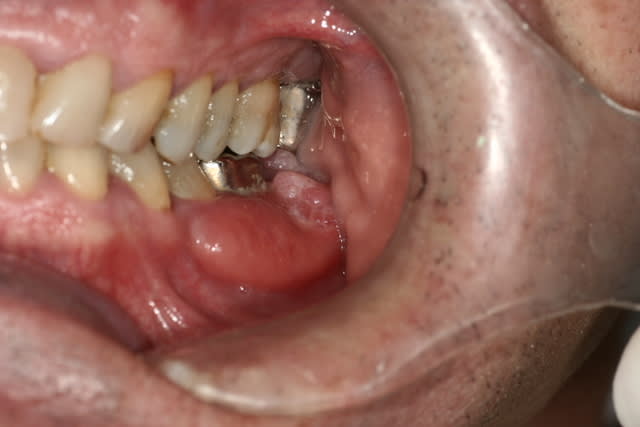

Présent depuis 1 mois, douloureux à la palpation en lingual, chaud et dépressible.

Pas de douleurs.

Il n'y aurait pas une lésion osseuse juste sous ces bourgeons???

Ca fait quand meme pas très bénin, non?

c'est moche mais c est pas ulcéré je pense pas que se soit malin ce truc

pas malin, c'est pas sur.

J'ai vu une fois un carcinome verruqueux qui avait cet aspect exterieur et le meme aspect radio.

comme pepe54 , envoi rapide en service hospitalier, je ne mettrais pas 10 kopeks sur un truc bénin.